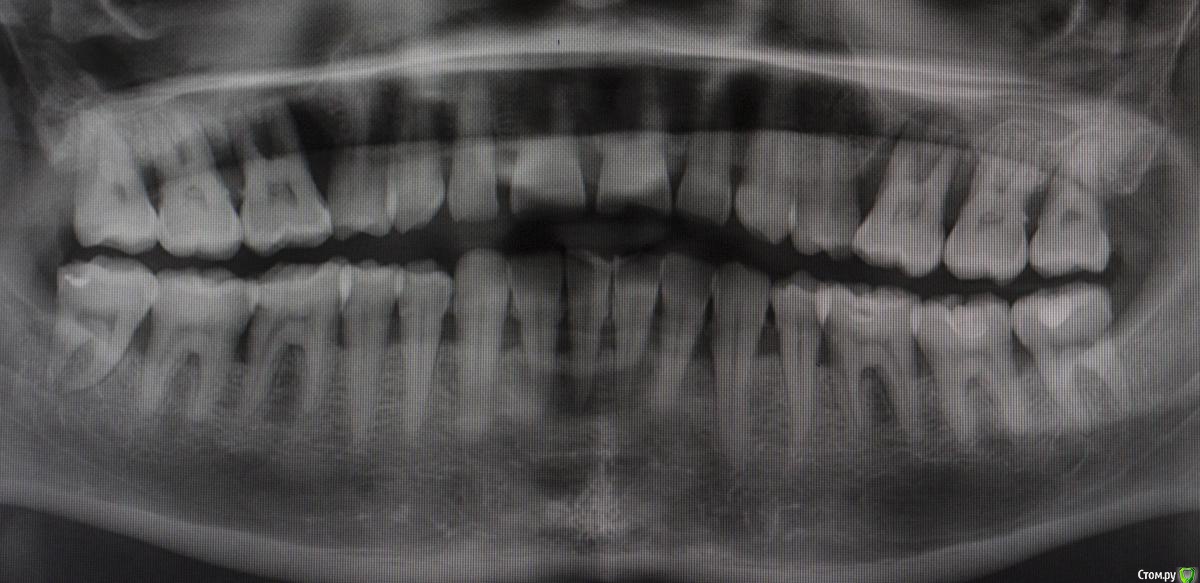

DmitrySH Опубликовано 28 июля, 2015 Автор Поделиться Опубликовано 28 июля, 2015 Визуально кариеса нет. Пациент из той группы, у которой зубы могут быть покрыты кучей налета, все желтого цвета, но кариесу мало подвержены.КТ делал, хотел понять что с костью вокруг зуба, что с пазухой. Небно абсцесс, все мягкое, отечное. Изначально думал, что только пародонтальная проблема. С гайморитом отдельно надо разбираться, с другой стороны в пазухе вообще просвета нет. Ссылка на комментарий

АнтонТЛТ Опубликовано 28 июля, 2015 Поделиться Опубликовано 28 июля, 2015 Да там как-будто кариозная полость сообщается с пульпарной камерой Ссылка на комментарий

diesel87 Опубликовано 28 июля, 2015 Поделиться Опубликовано 28 июля, 2015 Да там как-будто кариозная полость сообщается с пульпарной камеройХочешь сказать тупо прохлопанный периодонтит?) Ссылка на комментарий

diesel87 Опубликовано 28 июля, 2015 Поделиться Опубликовано 28 июля, 2015 Ну по данным срезам похоже, как на самом деле хз))И от него еще и гайморит?) Ссылка на комментарий

DmitrySH Опубликовано 29 июля, 2015 Автор Поделиться Опубликовано 29 июля, 2015 (изменено) Небно зондируется до апекса, на холод не реагирует, впрочем и перкуссия тоже отрицательна. Болит только слизистая небно. Сейчас пообщался, после вчерашней ревизии "кармана" все прошло, ничего не болит. Он в субботу еще в отпуск собрался Изменено 29 июля, 2015 пользователем dmitrySH Ссылка на комментарий